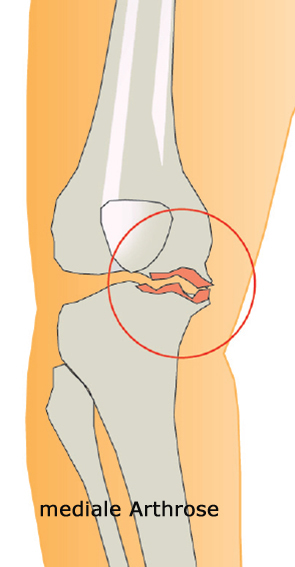

Arthrose des Kniegelenks

Die Arthrose des Kniegelenks ist ein schmerzhafter, deformierender Vorgang am Kniegelenk der durch Knorpelschwund Fehlstellung (X-Bein, O-Bein), Gelenksschwellung und Bewegungseinschränkung gekennzeichnet ist. Wenn konservative Behandlungsversuche fehlschlagen (siehe Rubrik Wissenswertes) ist oft der letzte Ausweg für den Patienten und den behandelnden Orthopäden die Gelenkersatzoperation (siehe Rubrik Leistungen).